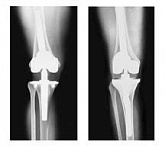

Endoprothetik des Kniegelenks

In den späten Stadien der Arthrose des Knies durch eine ausgeprägte Begrenzung der Bewegung begleitet, konstant starke Schmerzen, körperliche Unversehrtheit Verformung bis zur Genesung der einzige Weg ist der Ersatz des betroffenen Gelenks für eine künstliche - Endoprothetik.

Diese Methode ermöglicht es Ihnen, die richtige Form des Gliedes, eine vollständige Palette von Bewegung im Gelenke, zu entlasten ständige Schmerzen und Knirschen bei Bewegung und als Ergebnis wieder herzustellen, signifikant dem Patienten Lebensqualität zu verbessern.

Im Folgenden sind Röntgenaufnahmen und Fotografien, die die Strecke der Bewegung in der betroffenen Gelenke vor und nach der Operation veranschaulichen.